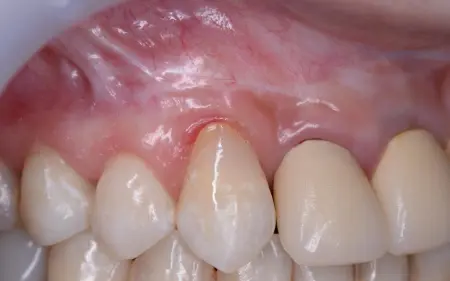

当院では、お口の中の健康とお口周りの美しさをトータル的に考えた治療を心がけています。歯科医院の目的は、虫歯・歯周病の歯の治療です。しかし最も力を入れるべきことは、虫歯や歯周病にならないための予防指導だと考えます。 プラークコントロールや歯の健康診断を定期的に受けることで大切な歯を守れるのです。丈夫で健康な歯は、何でも美味しく食べることができ、いつまでも若々しい口元と笑顔を保てます。当院の指導で、ご自分の歯で末永く健康にいきいきお過ごしいただきたいと思っています。